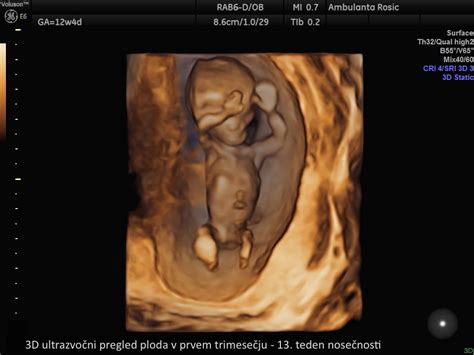

- 3D/4D ultrazvok: Ti naprednejši ultrazvočni pregledi omogočajo bolj realističen prikaz ploda, vključno z obraznimi potezami, ter ocenjujejo njegovo vedenje in razvoj. Pogosto se ponujajo kot dopolnilna storitev ob morfologiji ali kot samostojen pregled.